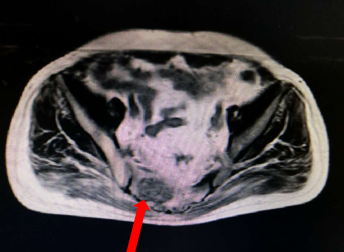

盆腔CT(2015.12.16)

直肠壁不规则增厚,局部肠腔变窄,盆腔内未见明确肿大淋巴结。

2016年6月患者出现肛门区疼痛,肿瘤标志物略增高,盆腔磁共振与前对比直肠病灶较前增大,骶椎转移瘤。